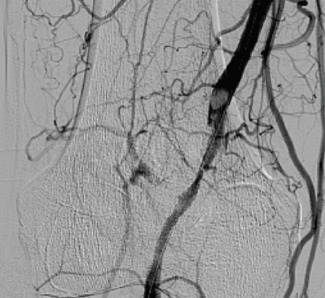

Rajeev Bhardwaj, MD, DM; Anupam Jogta, MD; Malay Sarkar, MD

We present a patient who underwent angioplasty of the entire length of the inferior vena cava.